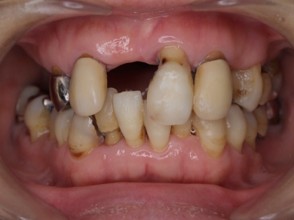

矯正治療・インプラント治療・セラミック治療・金属床(部分入れ歯)の症例紹介(三隅歯科クリニック)

| 主訴 | 50代女性 以前いれた入れ歯が合わなくて使っていないので、しっかり噛めるようになりたい |

| 治療内容 | 矯正治療、インプラント治療、セラミック治療、金属床(部分入れ歯)を行いました。 |

| 治療費 | 4,200,000円(税込み) |

| 治療期間 | 2年(矯正治療期間 1年) |

| 治療回数 | 50回 |

| 想定されたリスク | 重度の歯周病で臼歯部の歯槽骨がかなり吸収していたため、インプラントが脱落するリスクがありました。 |